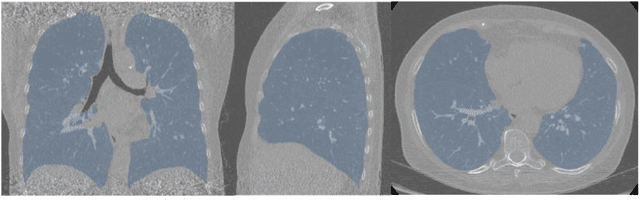

Segmentation of the bronchovascular bundle within the lung parenchyma is a key step for the proper analysis and planning of many pulmonary diseases. It might also be considered the preprocessing step when the goal is to segment the nodules from the lung parenchyma. We propose a segmentation pipeline for the bronchovascular bundle based on the Computed Tomography images, returning either binary or labelled masks of vessels and bronchi situated in the lung parenchyma. The method consists of two modules, modeling of the bronchial tree and vessels. The core revolves around a similar pipeline, the determination of the initial perimeter by the GMM method, skeletonization, and hierarchical analysis of the created graph. We tested our method on both low-dose CT and standard-dose CT, with various pathologies, reconstructed with various slice thicknesses, and acquired from various machines. We conclude that the method is invariant with respect to the origin and parameters of the CT series. Our pipeline is best suited for studies with healthy patients, patients with lung nodules, and patients with emphysema.